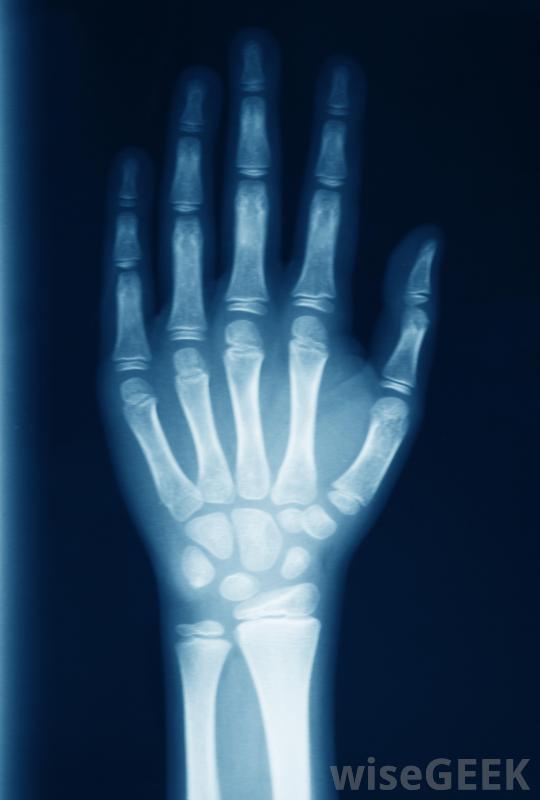

醫生通常會拍x光片,以確定拇指脫臼的最佳治療方法。許多醫生還建議在脫臼的拇指。要做到這一點,在拇指下面的手掌上敷一塊冰袋。如果沒有現成的冰袋,任何冷的或冷凍的東西都可以,比如一袋冷凍蔬菜這樣可以減輕疼痛,減輕患處的腫脹。

拇指脫臼的人應盡量避免打字用夾板夾住大拇指時,盡可能使其保持原來的位置。如果沒有可用的拇指或手指夾板,可用直的、平的、硬的棍子,例如冰棍,捏一下就可以了。先把木棒輕輕地放在手掌上,跟著大拇指。然后你可以把夾板粘在拇指上,先把拇指尖粘到夾板上。然后用膠帶把夾板底部粘到拇指關節上,最后包裹拇指,夾板,手上用繃帶或紗布即使你認為脫臼并不嚴重而且會自行愈合,強烈建議立即就醫,以防止進一步、更永久性的損傷。當你為拇指脫臼尋求治療時,醫生可能會做的第一件事就是拍x光片,這樣他就能看到損傷的程度,包括你有沒有骨折。脫位可以是簡單的,也可以是復雜的。如果是簡單的拇指脫位,韌帶通常會被拉伸或輕微撕裂。這種脫臼的拇指被認為是最容易治療的,通常只需要醫生將拇指移回關節。很多時候,拇指需要固定,通常用石膏固定大約三周。之后手指慢慢地移動會回來。復雜的拇指脫位通常會更嚴重一些,因為至少有一條韌帶完全撕裂。大多數情況下,修復損傷需要手術。手術后,拇指通常需要固定長達6周。有些患者可能還需要進行物理治療以恢復整個活動范圍。

醫生可以確定拇指是否脫臼,扭傷或折斷。